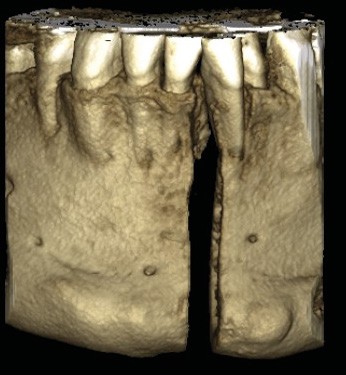

Le Dr Christophe Dunglas développera ensuite l’intérêt du cone beam lors de la mise en place des canines incluses difficiles. En effet, la préparation d’ancrages adéquats et de gestes chirurgicaux a minima préviendra l’apparition de résorptions radiculaires et de lésions parodontales.

Cette imagerie moderne montrera encore toute sa pertinence, au cours de la présentation du Dr Arnaud Lafon qui nous fera partager son expérience des transplantations dentaires. Longtemps considérée comme le « marronnier » de l’orthodontie, cette technique bénéficie maintenant d’un protocole bien établi et se révèle être une alternative très intéressante à l’implantologie, notamment chez les adolescents ou en cas de budget réduit. Solution immédiate, elle est parfaite lors d’avulsions des premières molaires mandibulaires cariées dans un protocole ortho-chirurgical. Plus besoin d’attendre la mise en place des troisièmes molaires pour envisager le geste de propulsion mandibulaire !